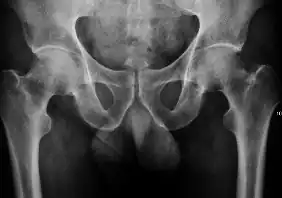

Projectional radiography ("X-ray") is the first imaging technique of choice in hip pain, not only in older people with suspected osteoarthritis but also in young people without any such suspicion. In this case plain radiography allows categorization as normal hip or dysplastic hip, or with impingement signs, pincer, cam, or a combination of both.[1]

X-Ray

Projectional radiography ("X-ray") is currently useful not only in older people in whom osteoarthritis of the hip is suspected but also in younger people without osteoarthritis, who are being evaluated for femoroacetabular impingement (FAI) or hip dysplasia.[1]

Plain radiography allows us to categorize the hip as normal or dysplastic or with impingement signs (pincer, cam, or a combination of both). Besides these, pathologic processes like osteoarthritis, inflammatory diseases, infection, or tumors can also be identified (Figure 1).[1]

Figure 1.

-

Radiography in normal hip -

X-ray in pincer impingement type of hip dysplasia -

X-ray of cam -

Hip in osteoarthritis -

Septic arthritis

- Osteoarthritis

In adults, one of the main indications for radiographs is the detection of osteoarthritic changes (Figure 1(e)). Nevertheless, radiographs usually detect advanced osteoarthritis that can be graded according to the Tönnis classifications. The grading system ranges from 0 to 3, where 0 shows no sign of osteoarthritis. Intermediate grade 1 shows mild sclerosis of the head and acetabulum, slight joint space narrowing, and marginal osteophyte lipping. Grade 2 presents with small cysts in the femoral head or acetabulum, moderate joint space narrowing, and moderate loss of sphericity of the femoral head. Grade 3 is the severest form of osteoarthritis, which manifests as severe narrowing of the joint space, large subchondral cyst with productive bone changes that may lead to deformity of the bone components of the joint, while secondary osteoarthritis due to calcium pyrophosphate deposition can be diagnosed when calcification of hyaline cartilage and fibrocartilage is detected.[1]

There are other pathological conditions that can affect the hip joint and radiographs help to make the appropriate diagnosis. Acute bacterial septic arthritis can be diagnosed by radiographs when a fast regional osteoporosis and destructive monoarticular process develops (Figure 1(f)). In case of tuberculous or brucella arthritis it is manifested as a slow progressive process, and diagnosis may be delayed.[1]